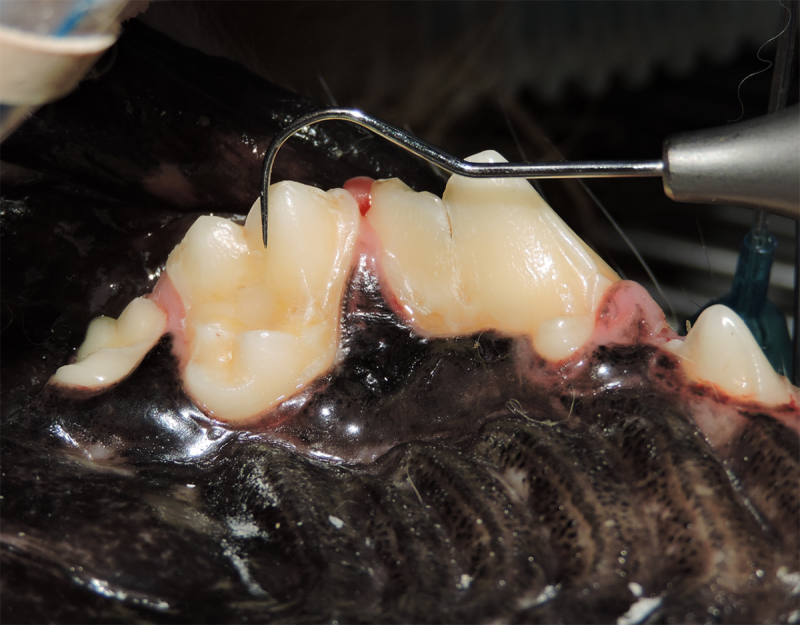

Root Canal Therapy

Root canal therapy is an excellent option for saving important teeth that have been fractured or are determined to be non-vital. The procedure is performed exactly as it would be for a human, except your pet will be dreaming peacefully under anesthesia. In many cases, root canal therapy is much easier on your pet than extraction, and preserves the structure of the tooth. It is important to have the root canal x-rayed periodically to monitor for any problems.

Vital Pulp Therapy

Young dogs less than 1 year of age that have very recently (less than 48 hours) fractured a tooth may be a candidate for vital pulp therapy. This procedure keeps the tooth alive and is very minimally invasive. For best results, this procedure should be performed within 48 hours of the tooth fracture. If your pet is not a candidate for this procedure, root canal therapy can still be performed to preserve the structure and function of the tooth. Vital pulp therapy can also be used to treat malocclusions.